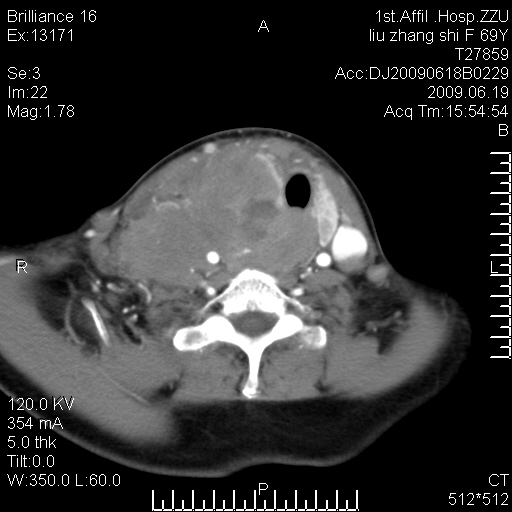

标题: CT26782:女,69岁,颈部占位,3天后公布病理结果。

【病理证实系列】女,69岁,颈部占位,有病理结果,3天后公布。(由于病例时间较久,临床资料不全,请网友见谅)本系列将有几百种常见、少见及罕见病例,均经病理证实。病例资料来自郑州大学第一附属医院。与网友共享,本人有空就发。

甲状腺癌并颈部淋巴结转移。感谢楼主的良苦用心,谢谢。

甲状腺癌并颈部淋巴结转移。

需与鼻咽癌鉴别!

支持甲状腺癌广泛侵及周围结构并颈部淋巴结转移。

鉴别:淋巴瘤、恶性神经源性病变、恶性纤维组织细胞瘤。

病理结果:颈部非霍奇金淋巴瘤。